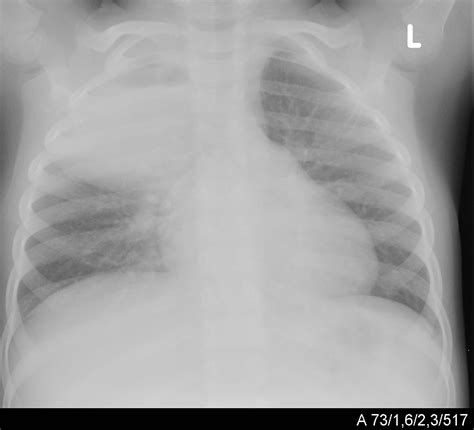

• Chest X-ray: Imaging the lungs to detect inflammation, fluid buildup, or consolidation.

A premature infant born at 28 weeks gestation developed pneumonia at three weeks of age. The infant was admitted to the neonatal intensive care unit (NICU) with symptoms of rapid breathing, fever, and lethargy. A chest X-ray confirmed the diagnosis of pneumonia, and the infant was treated with antibiotics and supportive care. After a two-week hospital stay, the infant recovered and was discharged home with close follow-up.